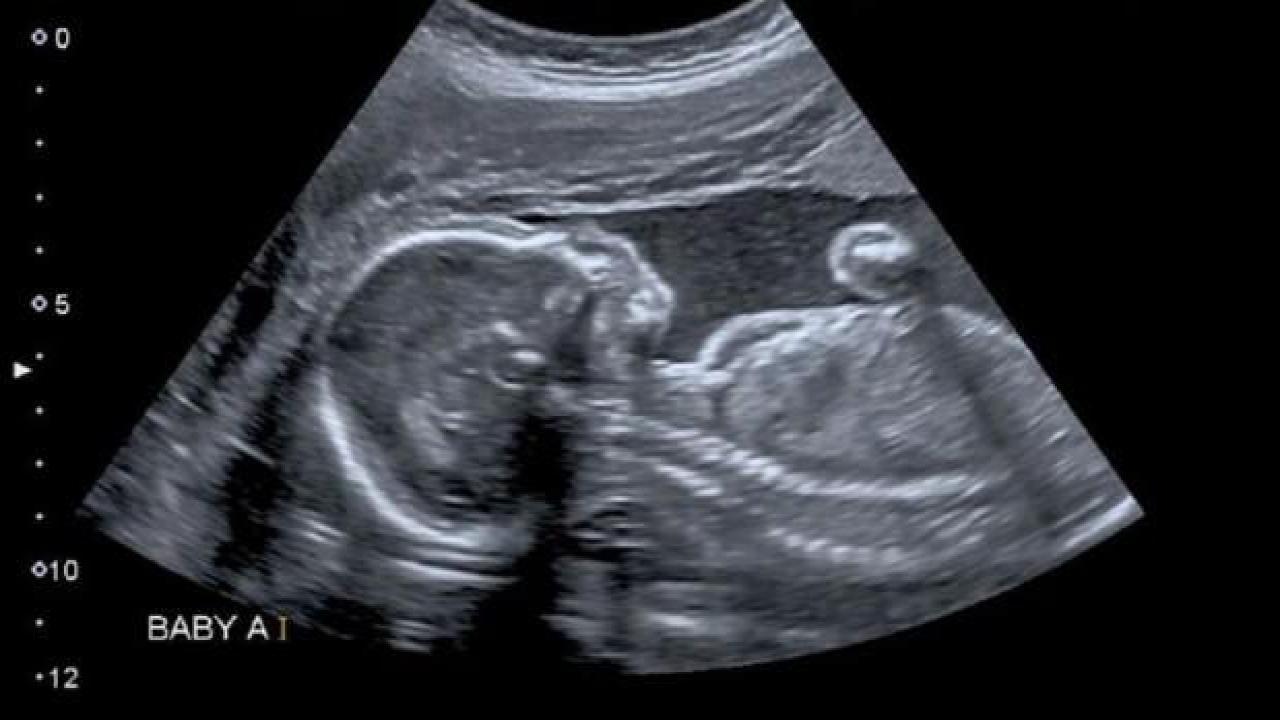

Doktorlar, ABD'nin Boston kentinde ülkenin tıp tarihine geçecek bir ameliyata imza atarak anne karnındaki bebeğe beyin ameliyatı gerçekleştirdi.Louisiana'da yaşayan Derek ve Kenyatta Coleman çifti, rutin kontrol için gittikleri hastanede doktorların olağan dışı bir şey fark ettiğini öğrendi.

Doktorlar, bebeğin beyninin içinde nadir görülen bir kan damarı anormalliği olan vasküler malformasyon olduğunu keşfetti.Bebeğin beynini gözlemleyen doktorlar, malformasyonun tehlikeli bir biçimde büyüdüğünü aktardı.Normal bir hamilelik süreci geçirdiğini düşünen anne Kenyatta'nın, karnındaki bebeği doğurmadan önce ameliyat edilip edilmemesine karar vermesi gerekiyordu.

Çiftin onay vermesiyle ameliyat gerçekleşti ve bebek sağlıklı bir şekilde dünyaya geldi. Bu işlem, ABD'de anne karnındaki bir bebeğe yapılan ilk ameliyat olarak tıp tarihine geçti.2018 yılında da Rus doktorlar, Tümen şehrinde anne karnındaki çocuğa beyin ameliyatı yapmışlardı.